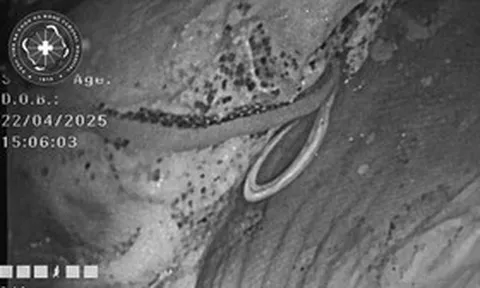

BS. Nguyễn Thị Thảo, Trung tâm Nội soi tiêu hóa và Thăm dò chức năng, người trực tiếp thực hiện thủ thuật cho biết: "Hình ảnh nội soi ghi nhận tại vị trí 1/3 trên thực quản, ngay sát phần cơ thắt trên về phía hầu họng, có một mảnh xương ngan kích thước khoảng 2×1,5 cm nằm chắn ngang lòng thực quản. Đáng chú ý, vùng niêm mạc tiếp xúc đã xuất hiện các vết trợt loét nhẹ do cạnh sắc của mảnh xương cọ xát".

Trước tình thế mảnh xương sắc nhọn có nguy cơ gây rách hoặc thủng thực quản nếu không khéo léo, ê-kíp bác sĩ đã sử dụng nội soi ống mềm, điều khiển dụng cụ gắp chuyên dụng để đưa dị vật ra ngoài thành công. Thủ thuật được thực hiện chính xác, đảm bảo không gây thêm tổn thương nào cho đường tiêu hóa.